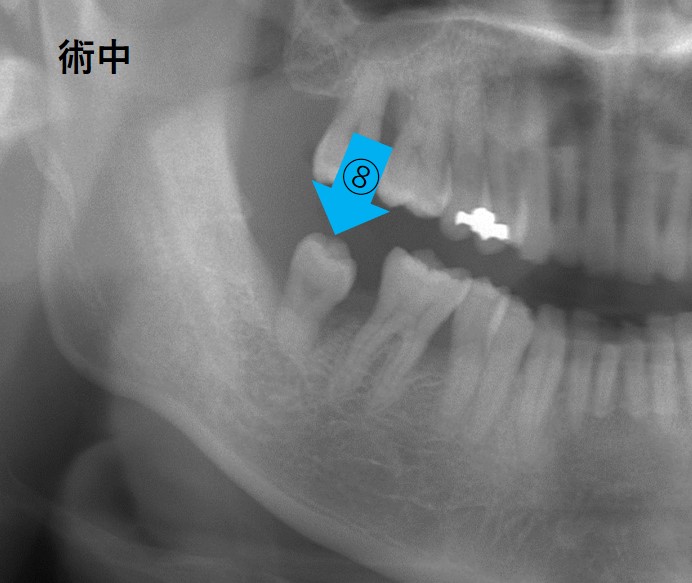

⑧が親しらずです。この⑧のせいで⑦が歯周病に罹患し、12mmの歯周ポケットができてしまいました。その結果、⑦の奥側の骨(歯槽骨)は吸収しています。

その原因は親知らずの生え方によります。親知らずが斜めに生えてしまったせいで、⑦の奥側にプラークが溜まって歯周炎を引き起こしてしまっているのです。

この場合、⑧を抜歯しても⑦の奥側の骨は吸収したままになり、⑦も⑧も共倒れになることが予想されました。

そこで、⑦を抜歯して⑧(親知らず)を移植する計画にしました。

移植直後の写真です。